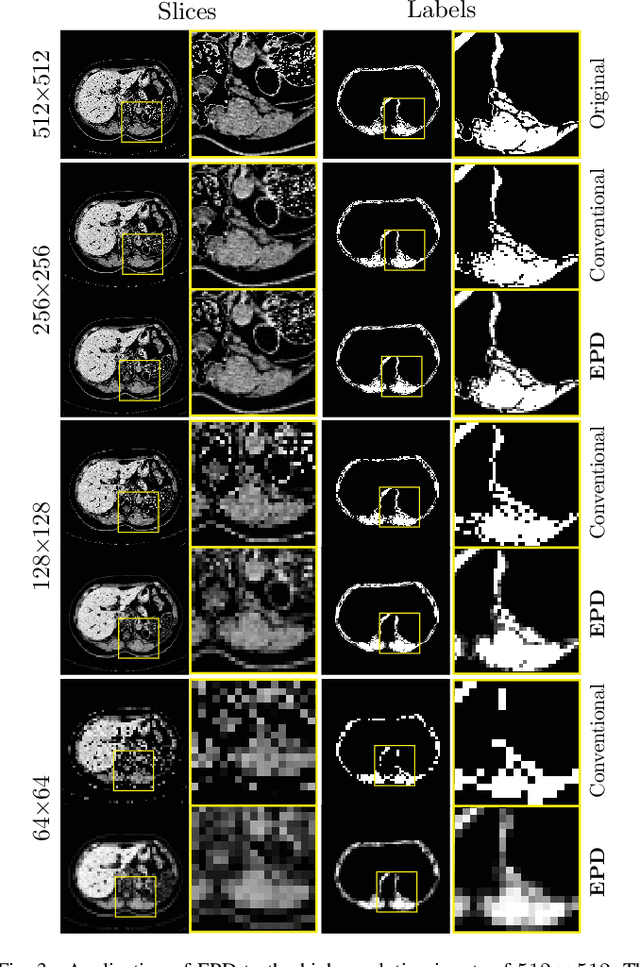

Abstract:Downsampling images and labels, often necessitated by limited resources or to expedite network training, leads to the loss of small objects and thin boundaries. This undermines the segmentation network's capacity to interpret images accurately and predict detailed labels, resulting in diminished performance compared to processing at original resolutions. This situation exemplifies the trade-off between efficiency and accuracy, with higher downsampling factors further impairing segmentation outcomes. Preserving information during downsampling is especially critical for medical image segmentation tasks. To tackle this challenge, we introduce a novel method named Edge-preserving Probabilistic Downsampling (EPD). It utilizes class uncertainty within a local window to produce soft labels, with the window size dictating the downsampling factor. This enables a network to produce quality predictions at low resolutions. Beyond preserving edge details more effectively than conventional nearest-neighbor downsampling, employing a similar algorithm for images, it surpasses bilinear interpolation in image downsampling, enhancing overall performance. Our method significantly improved Intersection over Union (IoU) to 2.85%, 8.65%, and 11.89% when downsampling data to 1/2, 1/4, and 1/8, respectively, compared to conventional interpolation methods.